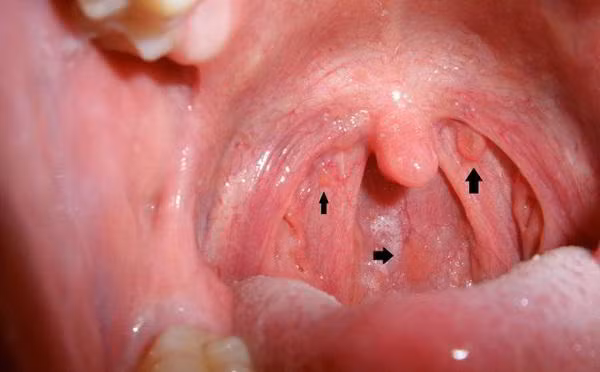

Đau rát họng, khản tiếng là một trong những dấu hiệu cảnh báo sớm ung thư vòm họng ngay ở giai đoạn đầu. Ảnh: ksol.

Dấu hiệu này chứng tỏ khối u đang phát triển gây tổn thương tế bào lành và chèn ép các cơ quan, chèn vào hạch bạch huyết gây đau rát họng khi nuốt nước bọt. Ảnh: kingfucoidan.